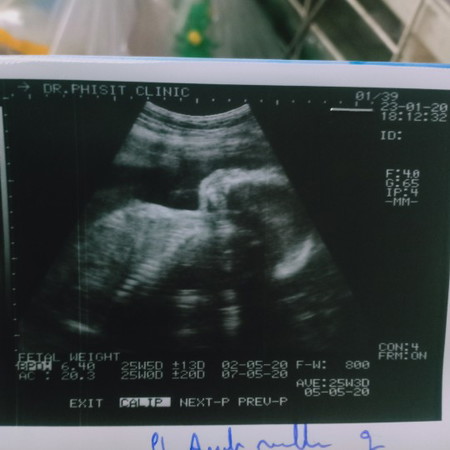

วันนี้ไปซาวมา คุณหมอบอกว่า น้องหนัก 800 กรัมแล้ว อยากรู้ว่าน้องหนักกว่าเกณฑ์หรือ ปกติคะ ตอนนี้ท้องได้ 25+1 6เดือนแล้วค่ะ